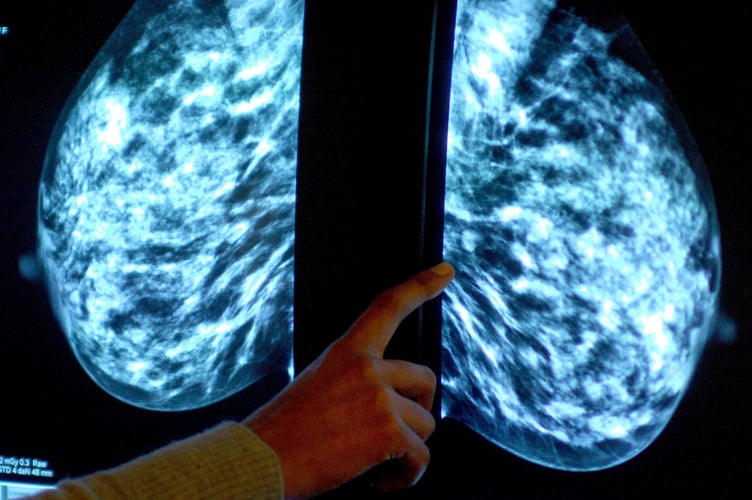

Breast screening uptake in Cornwall remains below pre-pandemic levels, new figures show.

It comes as charities have said women still face too many barriers to regular testing, as fewer people in England underwent tests than before the coronavirus pandemic

Anyone registered with a GP as female will be invited for NHS breast screening every three years between the ages of 50 and 71.